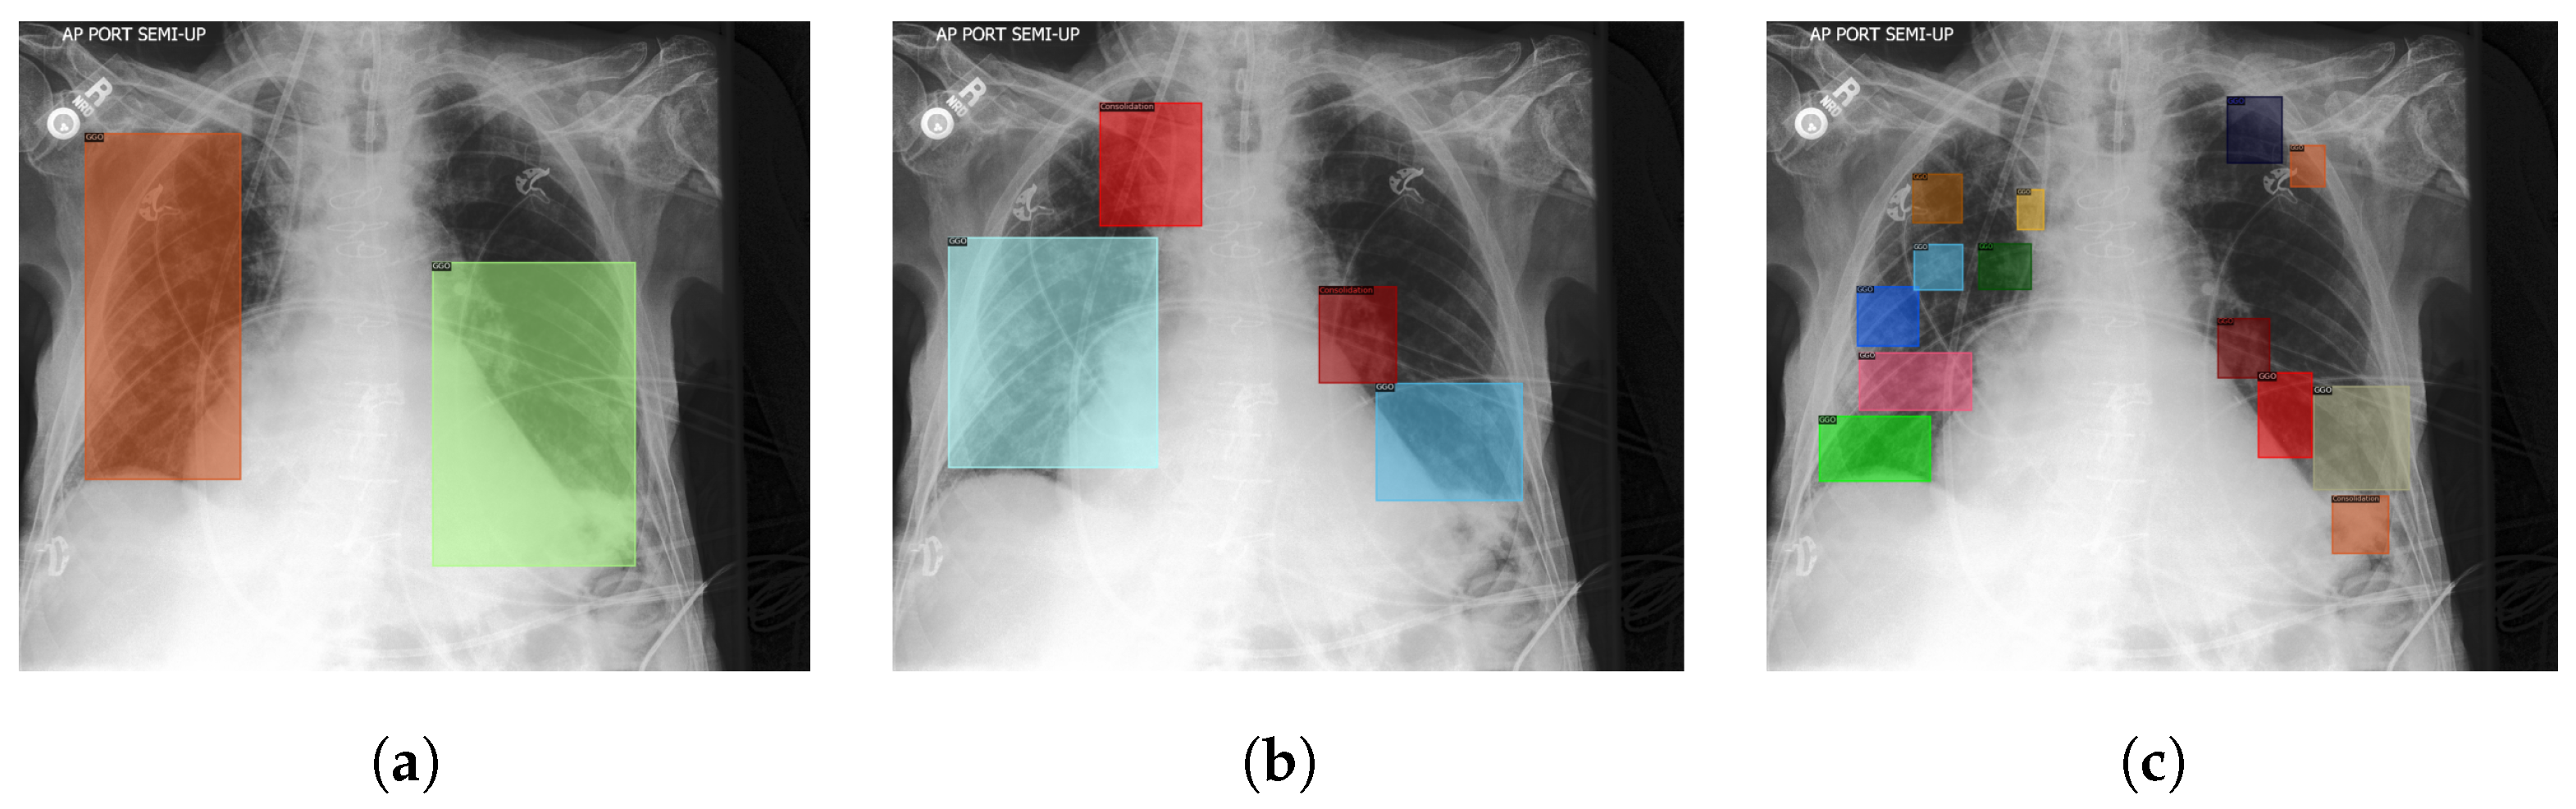

- To surpass the requirements of medical professionals and save a large amount of time required to annotate the COVID-19 lung lesion images, we developed our semi-self-supervised method. It leverages a prototype model from preliminary experiments (Teacher), which extracts the lung lesion features from pneumonia images, then helps us identify lung regions that potentially have lung lesions on unannotated COVID-19 CXR, in the form of pseudo-boxes. A novice annotator is supervised by these pseudo-boxes and then distills these boxes into the annotation data of COVID-19 CXR. Figure 1 illustrates our proposed method.

3.2. Semi Self-Supervised